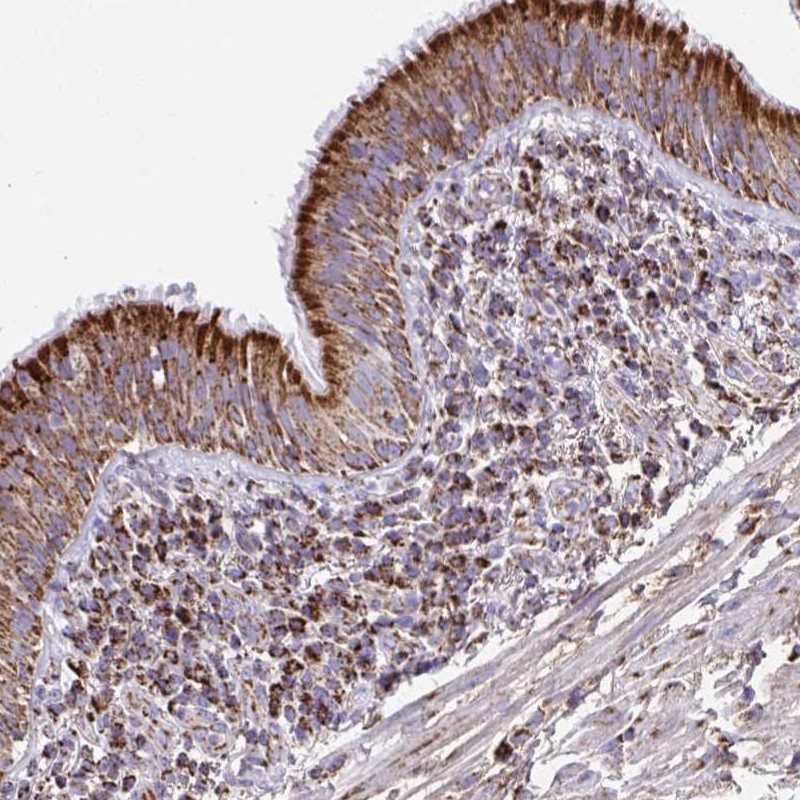

Immunohistochemical staining of human bronchus shows strong cytoplasmic positivity in respiratory epithelial cells.